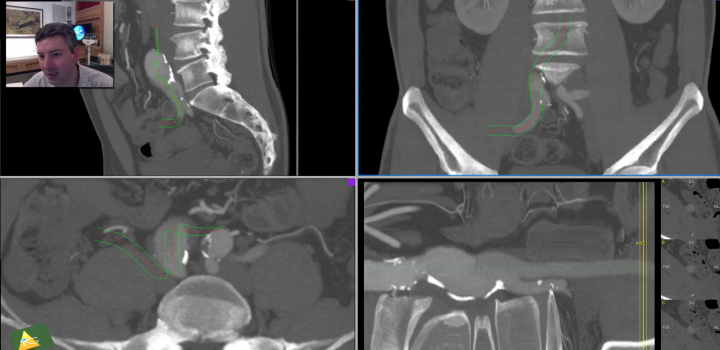

O 3D Curved MPR é a ferramenta que permite fazer o centerline manual no OsiriX.

É importantíssimo entender o 3D-MPR antes de passar para o 3D Curved MPR.